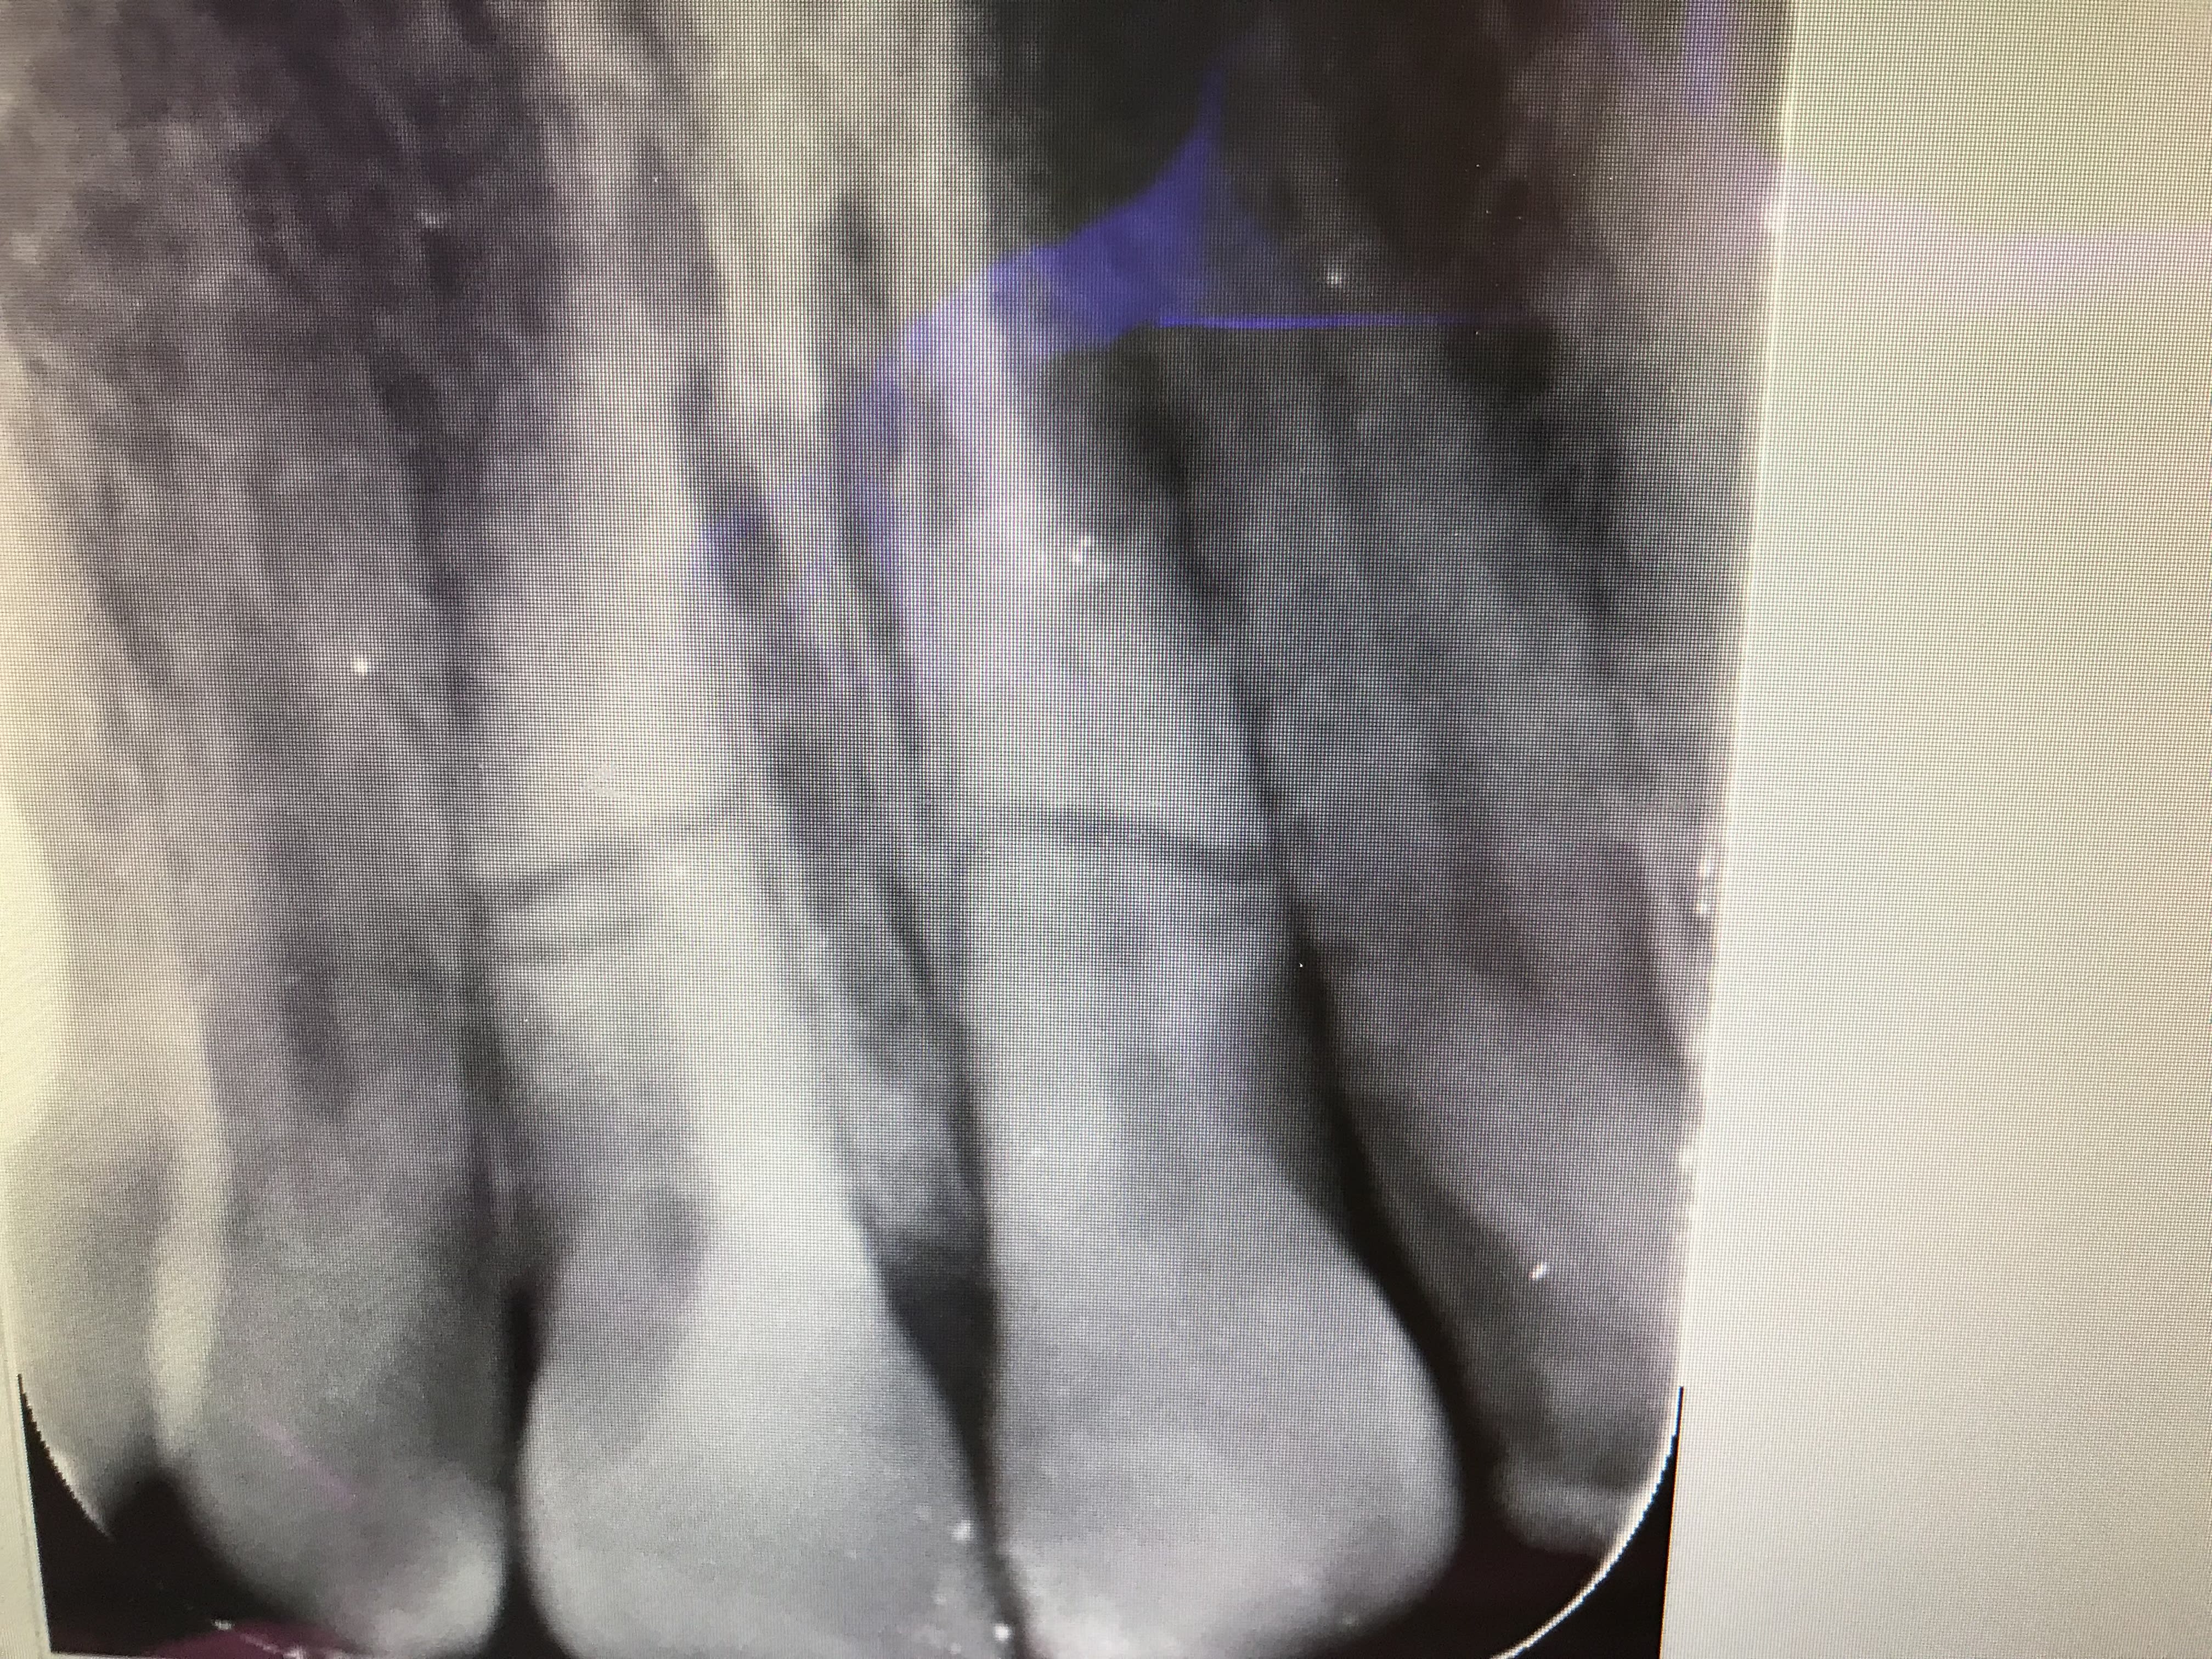

CasKiPu N°1:

Une 24 qui c'est fait mesialo-troué un troisième virtuel il y a un environ an chez un patient en pleine forme. Résine une dent ($$$) ou cobaye ? il dit cobaye :)

stabilité nickel , maxi patate en mesial, exo difficile car racine en forme de boursouflure coalesco-divergente.

Je dilate, ça sort.

visuellement c'est la merde:

- un cône de gutta

- une coulure de ce qui semble être un ciment composite

- un bouchon de MTA-like.

Coup de bistrac sur la racine, je gratoulle une couche de MTA et vu la coulure de compo je curète léger (ce que je ne fait jamais d'habitude) voir si il n'y aurai pas du rab.

J'enfourne ensuite au plus vite, deux point de superbond sur les adjacente (alvéole dilatée), un doliprane, ordo pour un cierge à la grotte et adishatz.